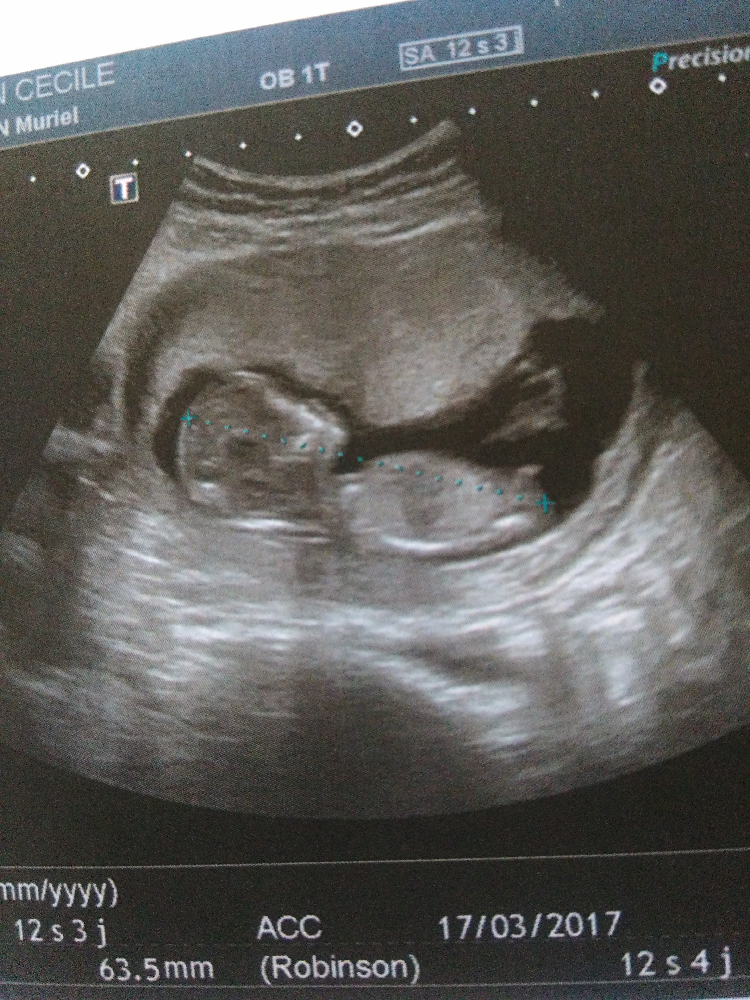

Vous allez pouvoir faire connaissance avec votre bébéJ'espère que c'est pas encore trop tôt j'ai une prochaine écho à 18 sa et je suis tellement impatiente de savoir les sexes de mes jujus j'espère trop que je pourrai le La première échographie de grossesse est réalisée entre 11 et 13 SA (semaines d'aménorrhée) 6 jours, "mais c'est entre 12 et 13 SA qu'il est le plus facile de faire les mesures requises", explique le Dr Emmanuelle BarraliGolstenne, échographiste gynécoobstétricale

Maman d'une adolescente en pleine puberté, d'une petite puce de 5 ans et d'un petit bonhomme de 6 mois, je suis une vraie pile électrique Faut que ça bouge tout le temps !Vous devriez tout de même passer une autre échographie entre 18 et 22 semaines de grossesse afin de fournir encore plus de détails sur la morphologie de votre bébé La première échographie montrera également si vous attendez un bébé, des jumeaux ou plus Il est toujours utile de savoir, le plus tôt possible, s'il s'agit d Echo 12 SA 3 jours le 27/07 bébé mesure 63cm et son coeur bat à 153p/m 80% de chances que tu sois une petite princesse On t'aime !

On la mesure lors du premier trimestre (jusqu'à 14 SA) Elle est de 55 mm en moyenne à 12 SA PC Périmètre Céphalique ou Crânien Il s'agit du tour de tête de votre bébé A la première échographie (12 SA) 68 mm en moyenne A la seconde échographie (22 SA) 199 mm en moyenne A la troisième échographie (32 SA) 297 mm en moyenneNous sommes aux anges /fontMoi 1er echo on nous annonce une fille Le mec etait sur Et a la suivante c etait un garçon Là gygy m'a dit qu'il était impossible d'être sur a la 1ere echo Les mamans qui ont eu une estimation du sexe à l échographie du 1er trimestre ç était garçon ou fille j ai l impression qu on voit plus les petits gars à 12Sa